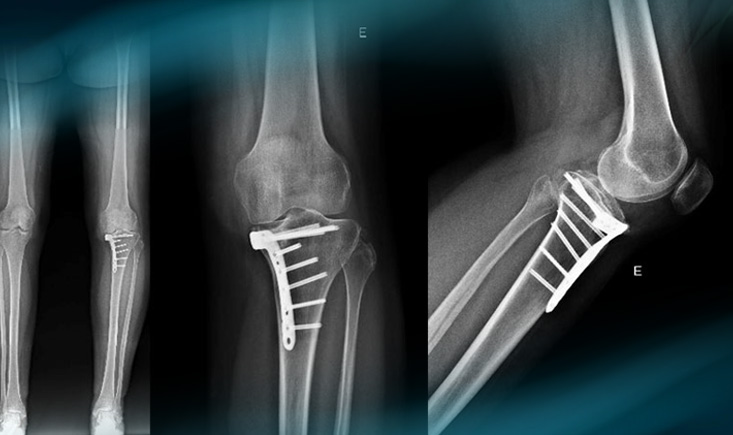

Pre-op Xrays

Pre-op Xrays​

Post-operative X-rays